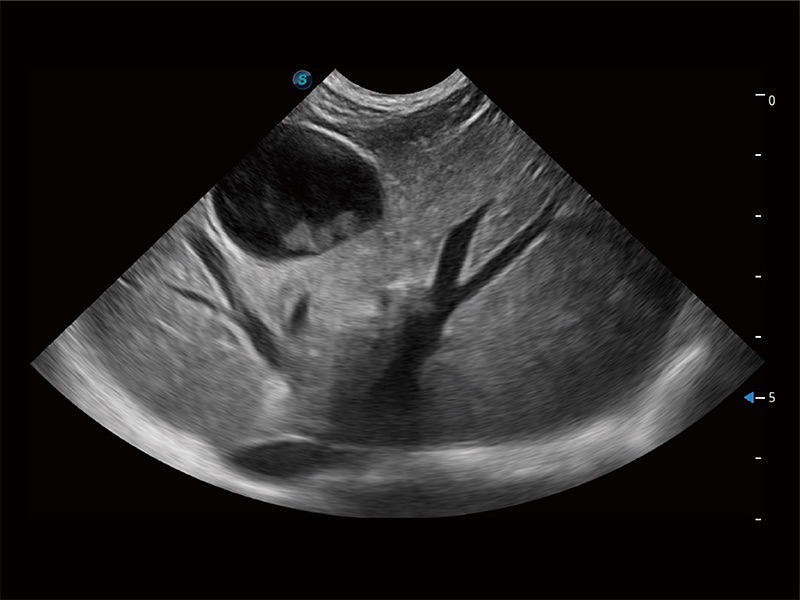

ProPet 80 配备了丰富的心脏探头群、先进的成像技术和专业的心脏测量工具,可帮助动物医生为不同体型和生理结构的动物提供心脏和心肌功能的全面评估。

非线性融合造影成像充分利用谐波和基波信号,为难以观察的血流进行增强显像。可用于线阵、凸阵、微凸阵、相控阵探头。